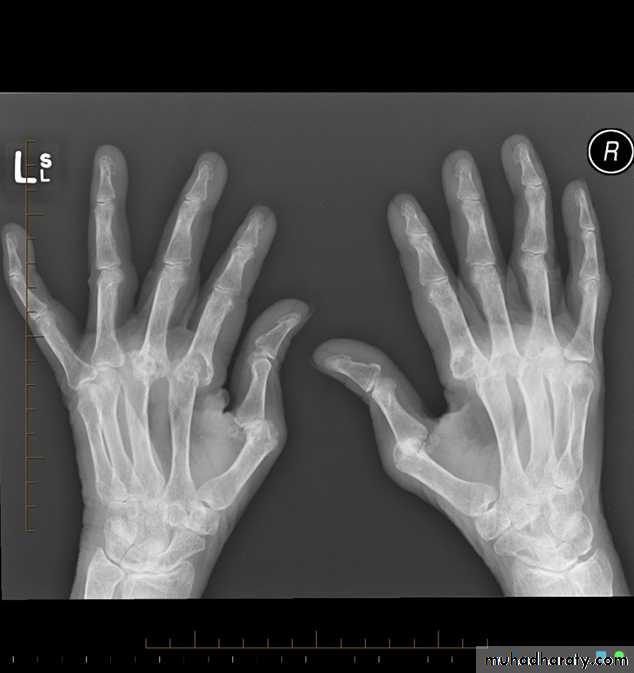

Rheumatoid arthritis. Bilateral changes are fairly symmetrical. Soft-tissue swelling is demonstrated, especially over the ulnar styloids. Erosions are demonstrated at the carpus, distal radius and ulna, with joint space narrowing and collapse of bone. Metacarpophalangeal erosions are also seen associated with joint space narrowing. There is a swan-neck deformity of the right fifth distal interphalangeal joint

Gross rheumatoid arthritis at the carpus with ulnar deviation,

subluxation and joint narrowing at the metacarpophalangeal joints.Boutonniere deformities are present at the index and little fingers.